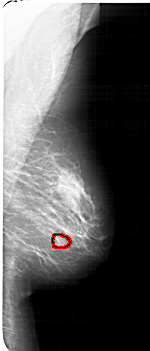

A_1770_1.LEFT_MLO

LEFT_MLO LINES 6406 PIXELS_PER_LINE 2956 BITS_PER_PIXEL 12 RESOLUTION 43.5 NON_OVERLAY

FILE: A_1770_1.RIGHT_MLO.OVERLAY

TOTAL_ABNORMALITIES 1

ABNORMALITY 1

LESION_TYPE MASS SHAPE OVAL MARGINS OBSCURED

ASSESSMENT 3

SUBTLETY 3

PATHOLOGY BENIGN

TOTAL_OUTLINES 1

BOUNDARY